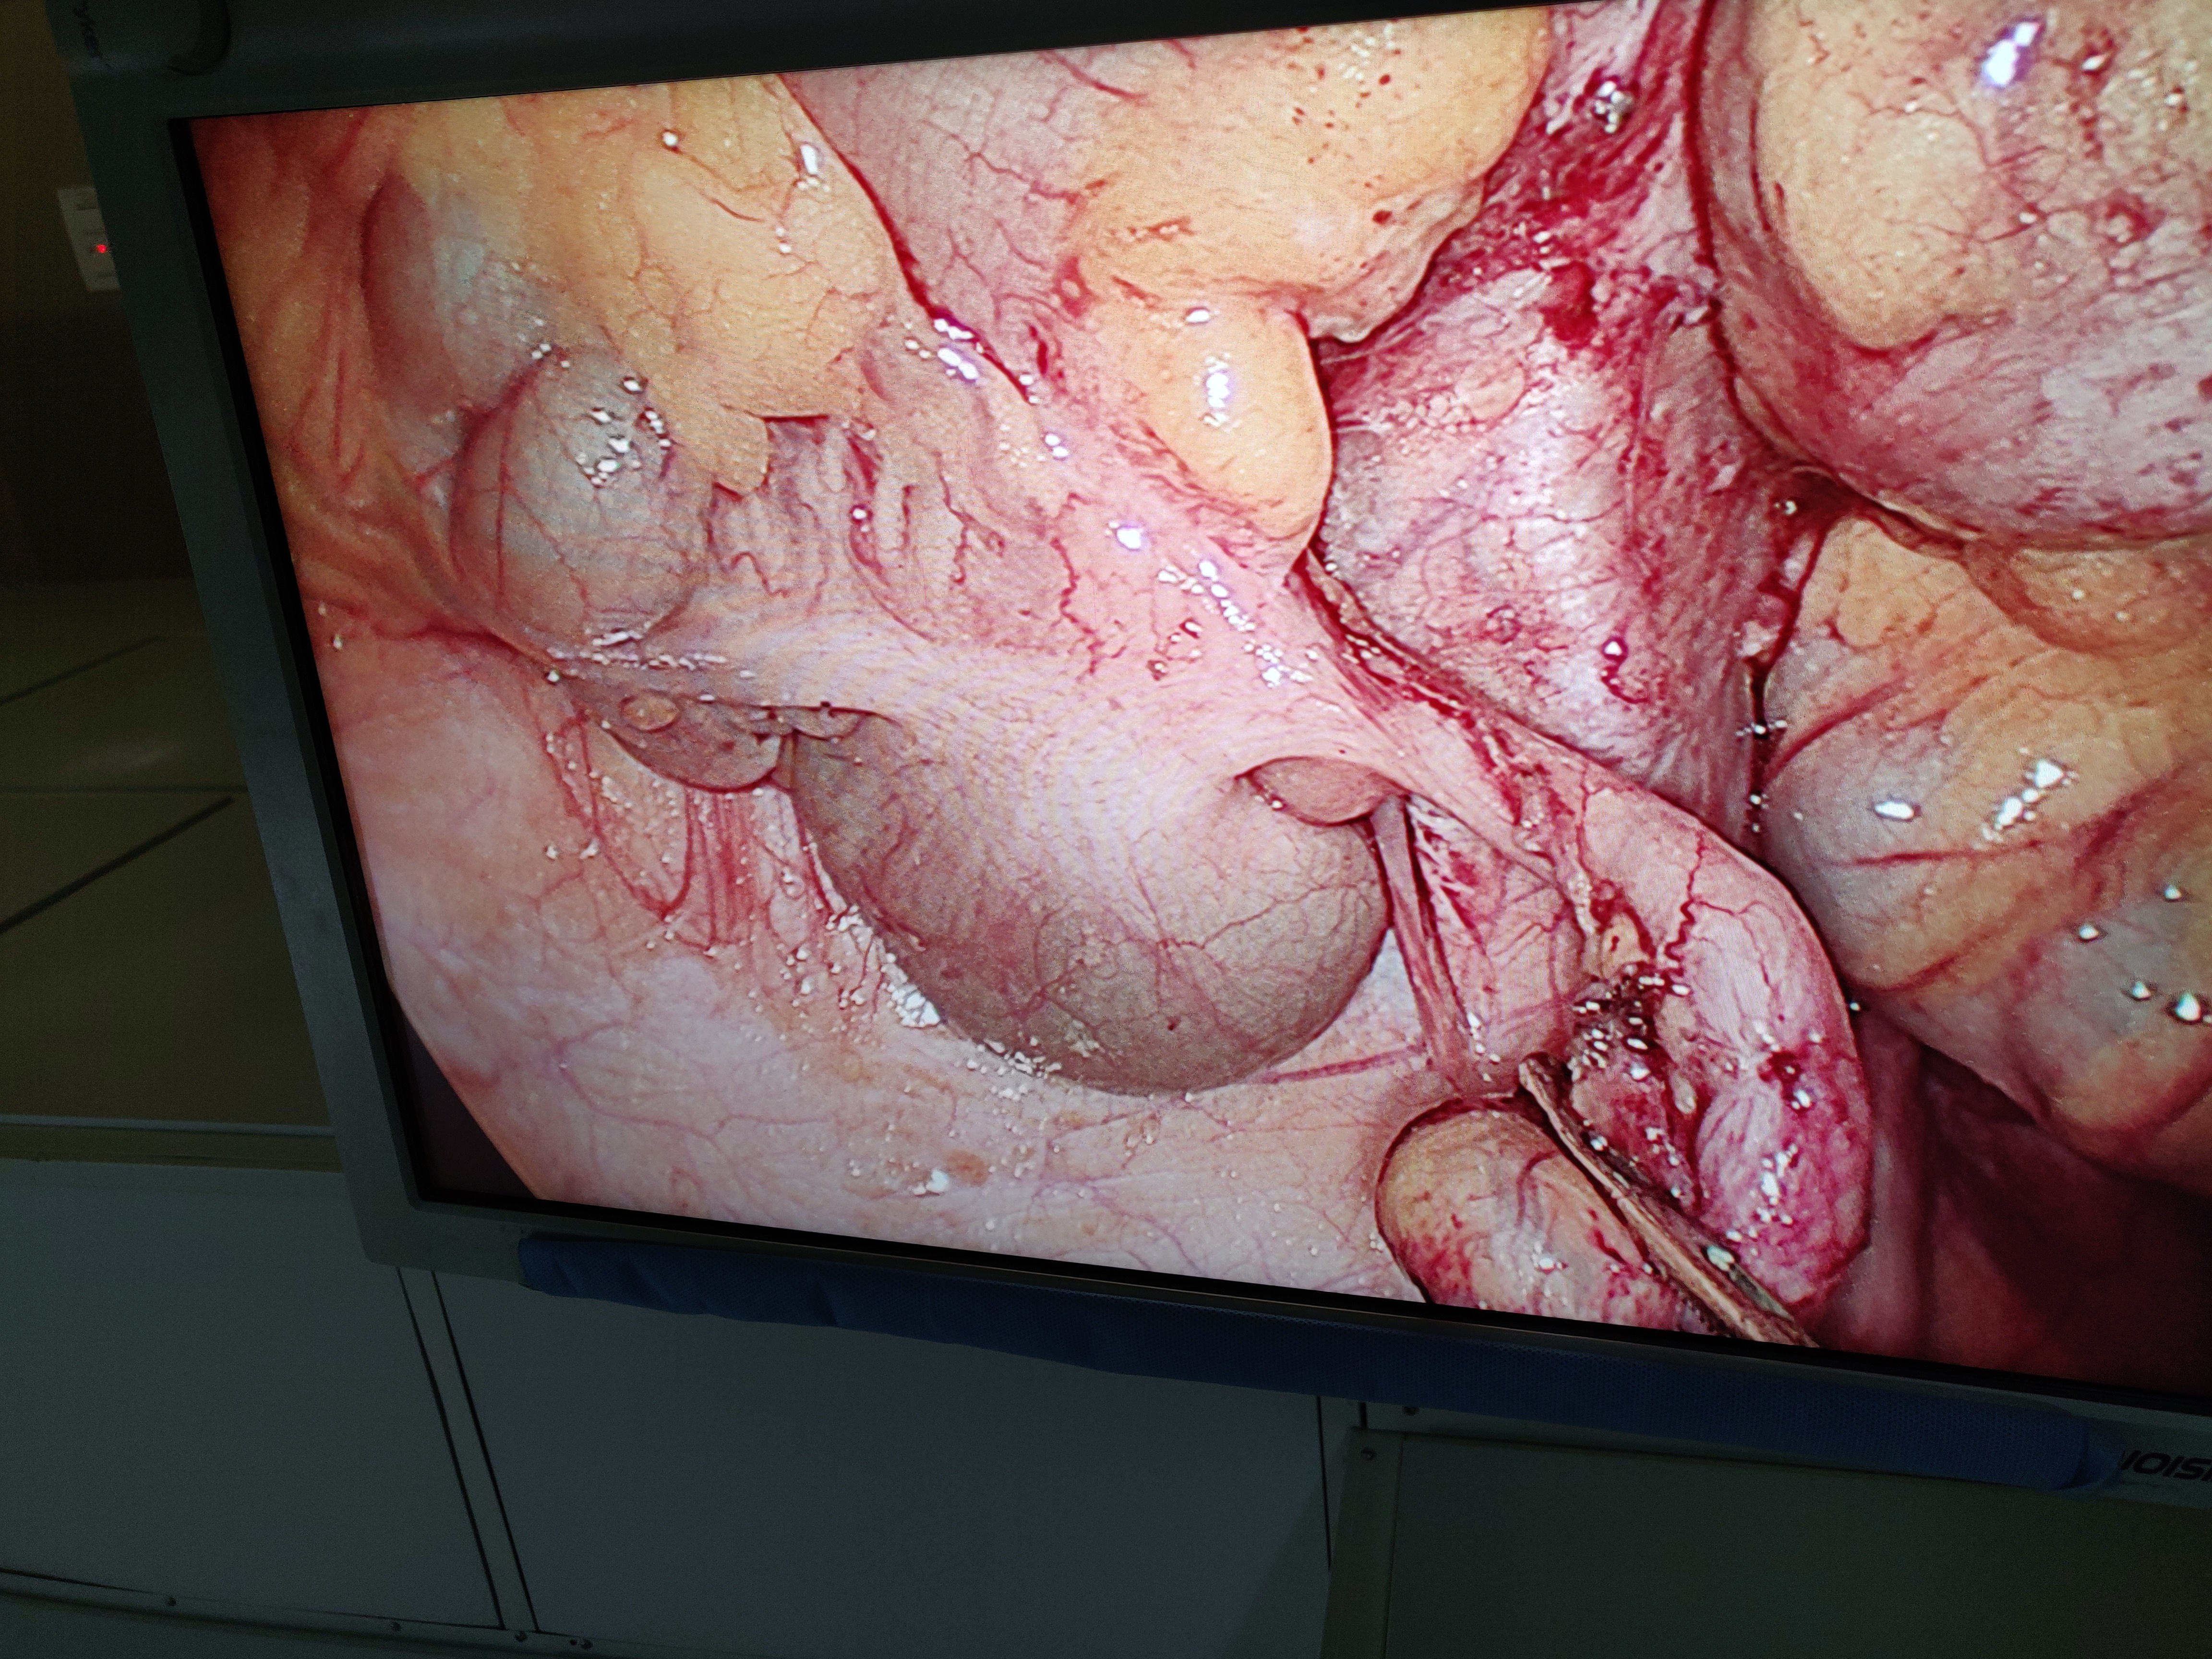

Dr. Pratik Biswas is a highly skilled and accomplished surgeon with an MBBS degree, DNB in General Surgery, and specialized training in Minimal Access Surgery (FMAS). His dedication to excellence is evident through his academic achievements and successful completion of programs from prestigious institutions like Holy Family Hospital and Zen Multi-Specialty Hospital. Dr. Biswas's commitment to staying updated in his field is further showcased by his completion of the FIAGES program. With a passion for surgery and a commitment to patient care, he is a trusted medical professional in the field.

Dedicated General Surgeon with special interest in Minimally Access Surgery. Efficient skills as an operative and assistant surgeon.

Minimally Invasive Surgery (MIS) is also used